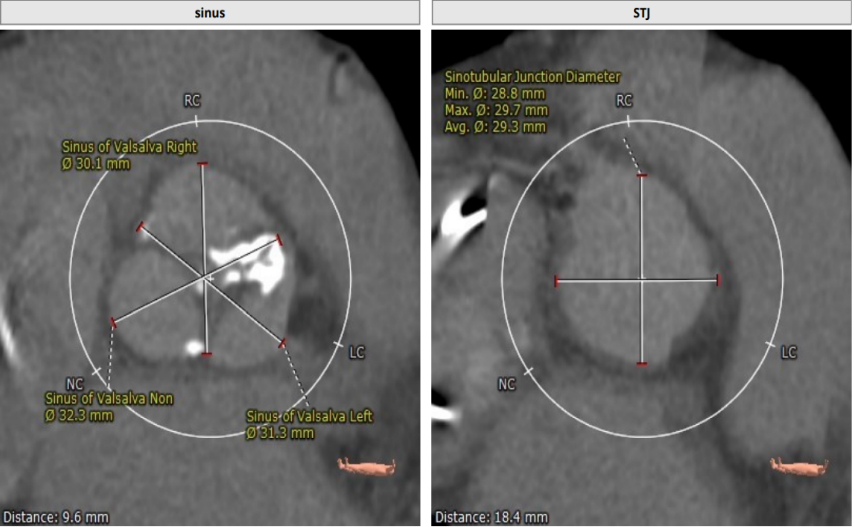

术前CT评估

TYPE 1型二叶瓣,中重度钙化,STJ:29.3